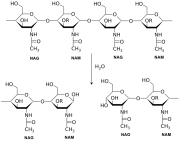

| 06:55, 26 במאי 2017 | Mecanism of action for Lysozyme.png (קובץ) |  |

25 קילו־בייטים | Motyk | 1 |